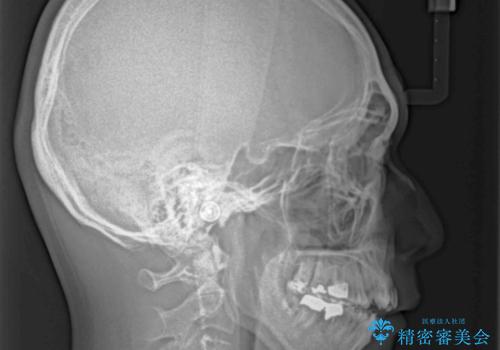

外科手術を併用した矯正治療を検討するほどに隙間の空いた開咬と、顕著な叢生が認められました。

開咬の改善には、舌の突出癖改善のためにトレーニングを行いつつ、インビザラインでの矯正治療が大変有効ですが、上顎骨が下顎骨に対して前方位に位置しており、インビザライン単独で治療を行うよりは補助装置とワイヤー矯正で奥歯の咬み合わせを改善してから、開咬改善のためのインビザライン矯正治療を行うこととしました。